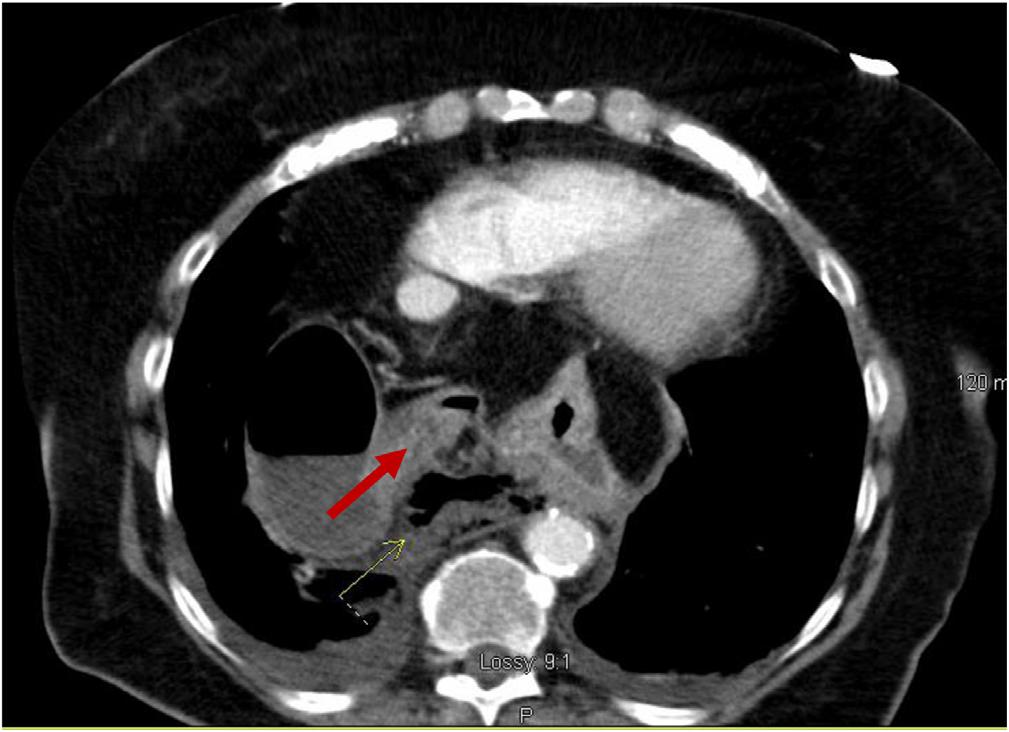

Achestradiograph(CXR)(Image1)showedalargehiatal herniawithtracebilateralpleuraleffusionsanddisplacement ofthegastricbubbletotheright.Computedtomography (CT)withcontrastofthechest/abdomen/pelvis(Images2 and 3)demonstratedalargehiatalherniawithmostofthe stomachinthechest,associatedvolvulus,bilateralpleural effusions,rightgreaterthanleft,andacomplex,partially fluid-filledcollectionalongtheposterioraspectofthehiatal

Anterior-posteriorchestradiographdemonstratinglarge hiatalherniawithdisplacementofthegastricbubble(arrow)from lefttoright.

Image3. Transverseviewofcomputedtomographyofthechest/ abdomen/pelviswithanarrowindicatingpartially fluid-filled collectionposteriortoalargehiatalherniasuspiciousfor esophagealperforation.

Image1. Image2. Coronalviewofcomputedtomographyofthechest/ abdomen/pelvisshowinglargehiatalhernia(arrow).Thepatientunderwentanexploratorylaparotomy,which confirmedthepresenceofanesophagealrupturenearthe squamocolumnarjunctionandrevealedthepresenceofa gianthiatalherniawithanassociatedupside-downstomach. Surgicalrepairoftheesophagealperforationandgastropexy wasperformed.Thepatientwasadmittedtothesurgical intensivecareunitforatotalof fivedaysduringwhich shehadanepisodeofatrial fibrillationwithrapidventricular responsethatresolvedaftermetoprololanddiltiazem.